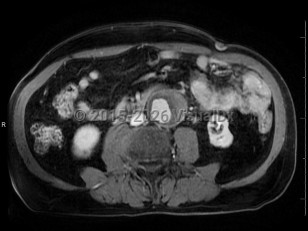

Pyelonephritis